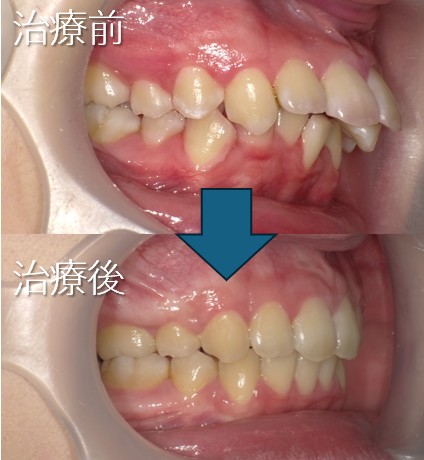

上の歯が前に出ている(上顎前突:いわゆる出っ歯など)

上顎前突:出っ歯

・主訴:出っ歯である

・診断:上顎前突

・年齢:20歳

・使用した主な装置:マルチブラケット装置

・抜歯部位:第一小臼歯を4本抜去

・治療期間:24か月

・通院回数:24回

・費用の目安:矯正料金として60万+税金。診断料金6.5円+税金。

調整処置料金:月3000円+税金を24回で7万2千円+税金。 第一小臼歯を4本抜去:1本5千円+税金。 総額 832.100円。

リスク・副作用:

・前歯の位置を修正するために、必要上、歯を減らします。

・虫歯にならない様に、通常の歯磨きを工夫することが必要です。

・歯が動く際に、歯のゆれを痛みとして感じることがあります。

・根の吸収が起きることがあります。

・保定をしないと後戻りが起きることがあります。